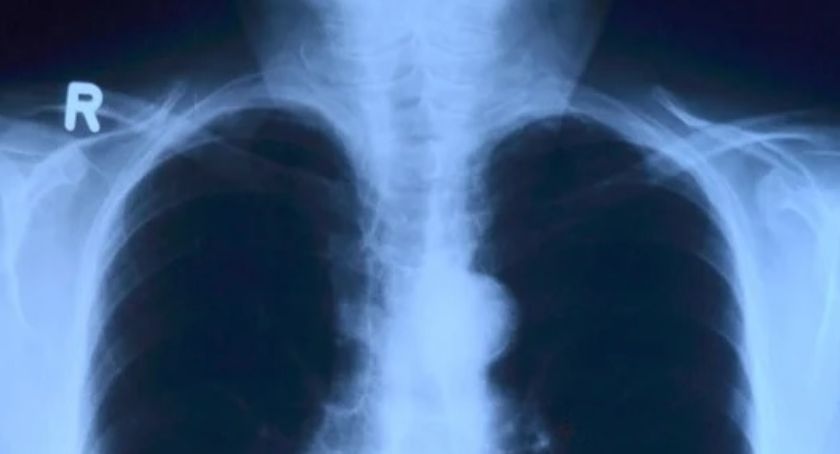

O potrzebach, jakie obecnie ma szczecinecki szpital, poinformował starosta Krzysztof Lis. Jak podkreślił, jedną z nich jest właśnie mocno wyeksploatowany aparat RTG. Urządzenie nie działa w sieci cyfrowej, a zdjęcia analogowe są trudniejsze do odczytywania. Aparat jest niezbędny przy wykonywaniu diagnostyki płuc.